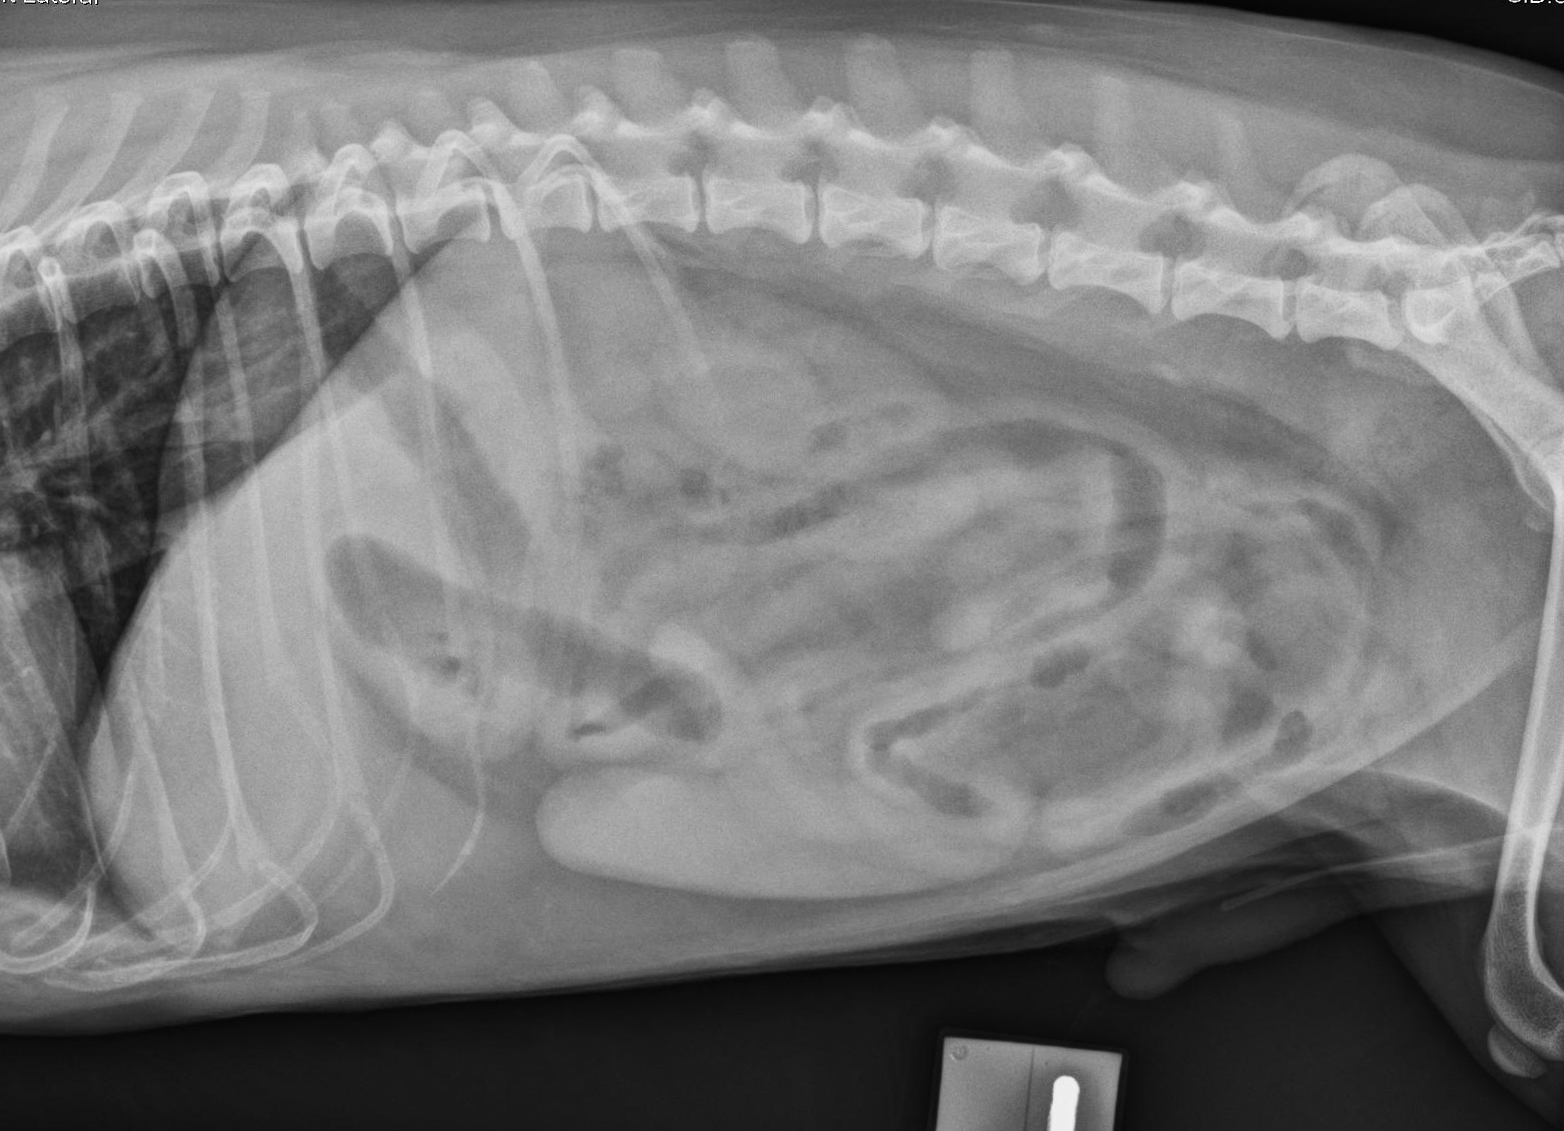

Latérale gauche